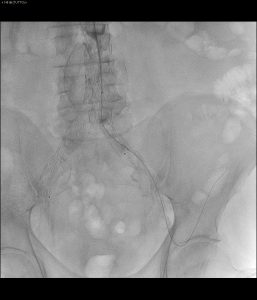

- By pass chirugico

- Controllo che mostra arteria renale non opacizzata

- Ricanalizzazione renale